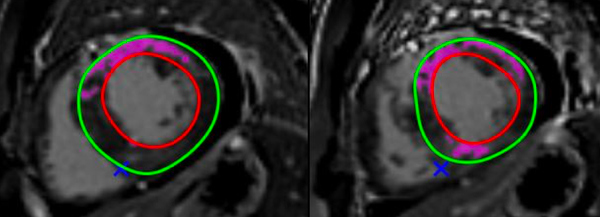

Non-Ischemic Cardiomyopathy

A lecture describing the role of CMR in the various non-ischemic cardiomyopathies